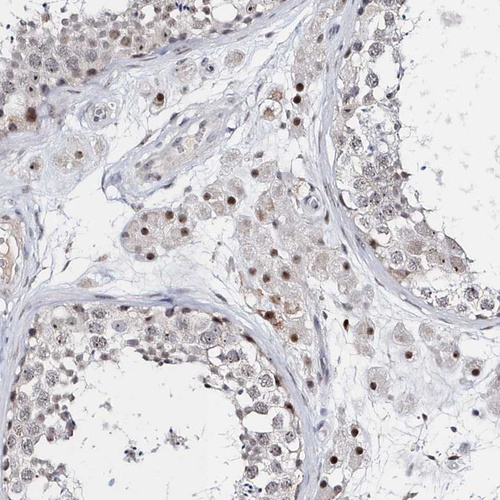

Immunohistochemical staining of human testis shows strong nuclear positivity in Leydig cells.